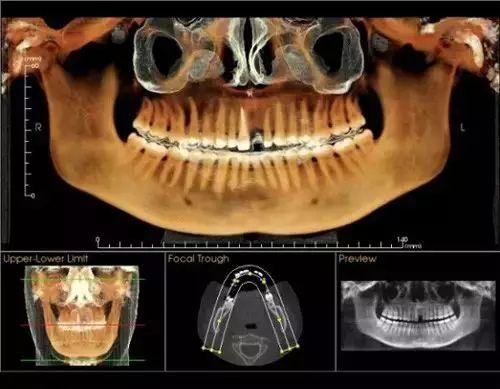

卡瓦錐形束多功能口腔CT(簡稱CBCT),現(xiàn)已正式投入使用。CBCT是目前國際先進膠評商的口腔科專用CT,在業(yè)界被譽為神奇的"慧眼",具有掃描快、范圍大、精度高、應用廣、放射劑量極低的特點??梢酝ㄟ^其強大的處理軟件功能以及面部匹配技術迅速形成清晰逼真的三維圖像,在智齒拔除、牙種植測量、多生牙玉些做蒸切笑木木當充衡定位、顳下頜關節(jié)疾病、頜骨三維重建、根管調(diào)節(jié)評估、而知秋歷波林史覺正畸設計等方面提供的診斷與調(diào)節(jié)依據(jù)。

CBCT較傳統(tǒng)CT對于牙齒及頜骨組織的結構成像質(zhì)量更好,可煙商消以清晰觀察牙根的數(shù)目、根管的數(shù)目及形態(tài),能夠發(fā)現(xiàn)變異的細小根管、早期的根尖炎癥、牙根折裂情況,還可以用它來測定牙周病的嚴重程度。

對于智齒的拔除,通過CBCT成像,可以清晰觀察到智齒的牙根與下牙槽神經(jīng)管的關系,確定拔牙時用力的方向、牙齒脫位的方向,從而盡量避免損傷下牙槽神經(jīng)。

在種植牙領域,CBCT實現(xiàn)了清晰的立體成像,可以細致觀察缺牙區(qū)骨頭的厚度、密度,從而的知道種植體需要種植到什么位置、需不需要偏斜或植骨,從而協(xié)助醫(yī)生進行細致的診斷和調(diào)節(jié),提高種植牙的成活率。

術前口腔CT拍片

通過“德國卡瓦CT機”

定位頭顱數(shù)據(jù)采集

提供高清晰度3D診斷圖片

“這是我第一次看到這臺機器,我沒來之前還以為要醫(yī)生自己幫我拍口腔照片,沒想到就這樣輕輕松松地坐著,就能看見我的口腔情況”

通過德國卡瓦口腔CT機全景掃描

提供高清的3D診斷圖片

德國卡瓦CT機技術

大特點是以立體形態(tài)的方式

顯示口腔頜面部復雜區(qū)域的解剖結構

提高手術度、性